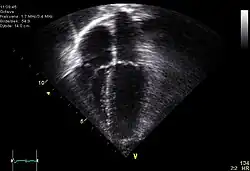

| Diagnostic method | ECG, chest x-ray, bedside echocardiogram |

In the setting of trauma, cardiac tamponade results from an acute pericardial effusion, the accumulation of blood within the sac that surrounds the heart. As this sac is filled with fluid, the pressure on the heart is increased, and the chambers of the heart are unable to fill with blood.

Diagnosis of traumatic cardiac arrest is initially made with electrocardiogram with EMS or in the emergency department. Clinicians will also order diagnostic testing that may include chest x-ray, bedside ultrasound and echocardiogram, and blood gas levels. A type and cross will be ordered to match the patient to receive blood transfusion if necessary.